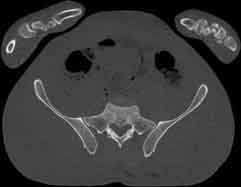

Visible Human male: Sectio transversalis 1778

CT